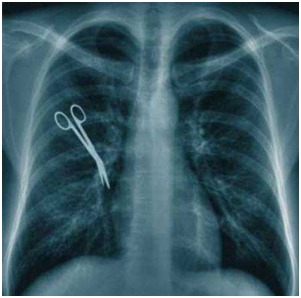

Errores por conteo inexacto después de una cirugía, que puede llevar a que algún instrumental o material se haya podido quedar en el cuerpo del paciente. Propuesta: Si el paciente siente dolor, fiebre o inflamación, vaya al hospital y pregunte a su cirujano.